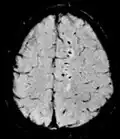

T1 e T2

Cada tecido retorna ao seu estado de equilíbrio após a excitação pelos processos independentes de T1 (spin-tretice) e T2 (spin-spin) de relaxamento. Para criar uma imagem ponderada em T1, a magnetização pode ser recuperada antes de medir o sinal MR, alterando o tempo de repetição (TR). Esta ponderação de imagem é útil para avaliar o córtex cerebral, identificando tecido adiposo, caracterizando lesões focais e, em geral, para obter informações morfológicas, bem como para imagens pós-contraste. Para criar uma imagem ponderada em T2, a magnetização pode decair antes de medir o sinal MR alterando o tempo de eco (TE). Esta ponderação de imagem é útil para detectar edema e inflamação, revelando lesões de substância branca e avaliando a anatomia zonal na próstata e no útero.